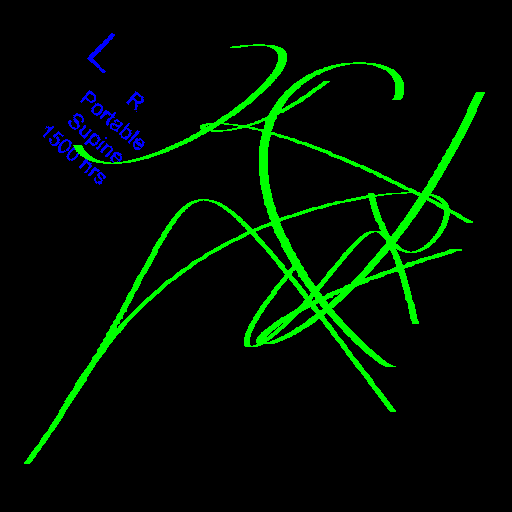

Automated catheter detection is a challenging task. Although most catheters have a radiopaque strip to facilitate detection, the strip may become less apparent depending on the projection angle. Catheters maybe confused by other similar linear structures like ECG leads and anatomy including ribs. Additionally, portions of catheters can be occluded by anatomical structures given that radiographs are a 2D projection of a 3D structure. For example, when a NGT is placed within the oesophagus, the catheter itself becomes less apparent due to the high density of the adjacent vertebrae. Finally, the number and type of catheters that could possibly appear in pediatric X-rays are unknown a priori. The catheters may be intertwined with each other thus making simple line tracing methods fail. Figure 1 gives three sample pediatric X-ray images with some common catheters highlighted in different colors.

To alleviate this annotation problem in catheter detection, we proposed to use X-ray images with simulated catheters by exploiting the fact that catheters are essentially tubular objects with various cross sectional profiles. To be more specific, a synthetic 2D projection of a catheter is generated by first simulating a horizontal catheter profile and then using it as a brush tip to draw along a B-spline path. This generated catheter is then composited with an X-ray image serving as the training data. Another contribution of this work is a segmentation network that can inherently take into account multi-scale information. This network adopts a UNet-style form and contains a recurrent module that can process inputs with increasing scales111Our code is available at https://github.com/xinario/catheter_detection.git.. We have empirically shown that by iterating through the scale space of the input image, higher recall is achieved as compared to using a single scale. Details about the methods are discussed in Section 3. Three sample detection results are shown in Figure 1.

The test dataset is collected locally and only contains frontal chest-abdominal X-rays from patients < 4 weeks old. This is the most common radiograph obtained to confirm placement of catheters such as UACs and UVCs in neonates. Currently, the test set has 35 fully labeled images with different catheter types with sample images previously shown in Figure 1. All the annotated catheters (lines excluding ECG leads) are treated as the same class in the detection.

Qualitative visual examples of the raw catheter likelihood maps obtained directly from the network without any postprocessing are shown in Figure 5. It can be seen that the proposed network at the highest scale (scale 3) achieves the best visual appearance as compared to the other methods. The maps from the proposed network at scale 2 and scale 3 look much cleaner than w/oR and fcn8s. We would attribute this to the iterative refinement of the detection results by using the recurrent module. When comparing results from the proposed network at different scales, we can see that the likelihood map from the smallest scale contains almost all line-like structures, including not only catheters but also ribs and ECG leads. This is because catheters, ribs, ECG leads look similar at a smaller scale. These irrelevant line-like structures are gradually filtered out in higher scales because catheters, especially UVCs and UACs, begin to appear as two parallel edges whereas ribs and ECG leads continue to appear as a single solid line.

There are certain situations where our proposed method would fail. Figure 7 (a) and (b) show a partially detected NGT. This mostly likely resulted from the decreased visibility of the radiopaque strip. Figure 7 (a) also shows another failure situation where the inferior portion of the UVC is occluded by the abdomen. (c) shows the case of a falsely detected unidentified line and (d) shows part of the lateral aspect of the rib cage falsely identified as a catheter.